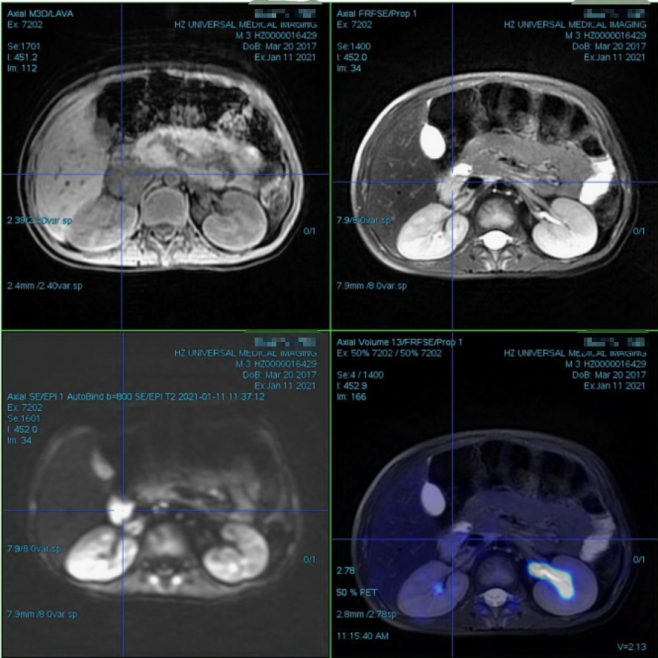

PET/MR(2021.1.11)

腹膜后右侧肾上腺区不规则团块,FDG代谢增高,考虑恶性病变,神经母细胞瘤可能性大,建议结合病理;腹膜后腹主动脉右旁数枚肿大淋巴结,FDG代谢增高,考虑转移;全身骨骼FDG代谢弥漫性增高,考虑骨髓浸润。